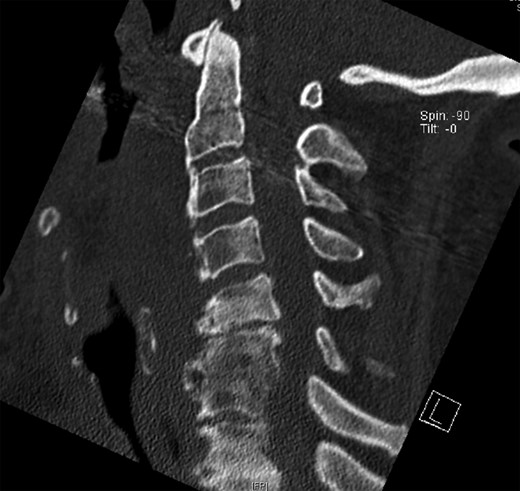

Surgical access to the cervical spine through a right-sided standard anterolateral approach showed osseous vegetations, which were strongly attached to the ventral spine and caused ventral displacement of the oesophagus. There was no infiltration of neighbouring tissues. Hyperostotic tissue at levels C3–C5 was carefully removed. Within 24 h, a single-dose 6-MeV photon of 7 Gy was applied. Indometacin treatment was initiated with 50 mg twice daily. A control CT examination showed successful removal of hyperostosis from segments C3 to C5 with intact vertebrae and proper configuration of the cervical lordosis without signs of instability (Fig. 4).

CT of the cervical spine in a sagittal view. Osteophytes from C3 to C5 are removed. Sagittal alignment of the spine is preserved.